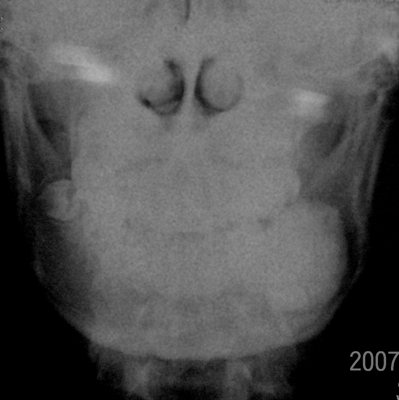

标题: X3060:男性,16岁,左侧下颌部肿痛十余日,左下颌硬性包块 [打印本页]

牙瘤又称齿瘤,牙体瘤较少见。是起源于牙胚上皮和间质细胞的混合性肿瘤发育第二萌牙期发育障碍,形成不规则牙齿或类牙团所致。其主要成分为牙釉质、牙本质、牙骨质、牙髓、纤维及骨组织。病理可分复合性牙瘤、牙骨质瘤、混合性牙瘤。肿瘤多存在于颌骨深部,早期不易发现,随着肿瘤增大,颌骨隆起,面部畸形。本肿物较大,压迫颏神经,引起下唇麻木,易误诊。

临床特点 (1)缓慢增大的骨质膨胀,一般较小,质硬,呈结节状,可有缺牙。(2)多无症状,少数压迫神经者可出现疼痛。 (3)x线摄片示骨质膨胀,有很多大小形状不同、发育不全的影像,或透射度似牙组织的一团影像,影像与正常组织间有一条清晰阴影,为牙瘤的被膜。复合性牙瘤比较罕见。

诊断依据:(1)缓慢增大的骨质膨胀,质硬,结节状,缺牙。 (2)多无症状,少数压迫神经者可出现疼痛。 (3)x线摄片示骨质膨胀,有很多大小形状不同、发育不全的影像,或透射度似牙组织的一团影像,影像与正常组织间有一条清晰阴影,为牙瘤的被膜。 (4)病理组织学检查确诊。

支持牙瘤,相应部位牙缺如,局部以较大骨化影为主要表现,边缘清,周围见透亮间隙,据报道有的牙瘤可以长到10cm